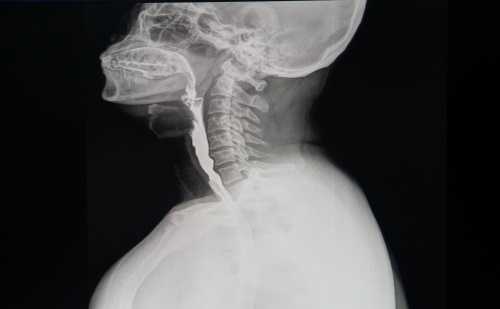

1-глотка (гортанная часть);

2-глоточно-пищеводный переход (верхнее сужение пищевода);

3-среднее (бронхо-аортальное) сужение пищевода;

4-нижнее (диафрагмальное) сужение пищевода;

5-диафрагма;

6-кардиальная часть (кардия) желудка.